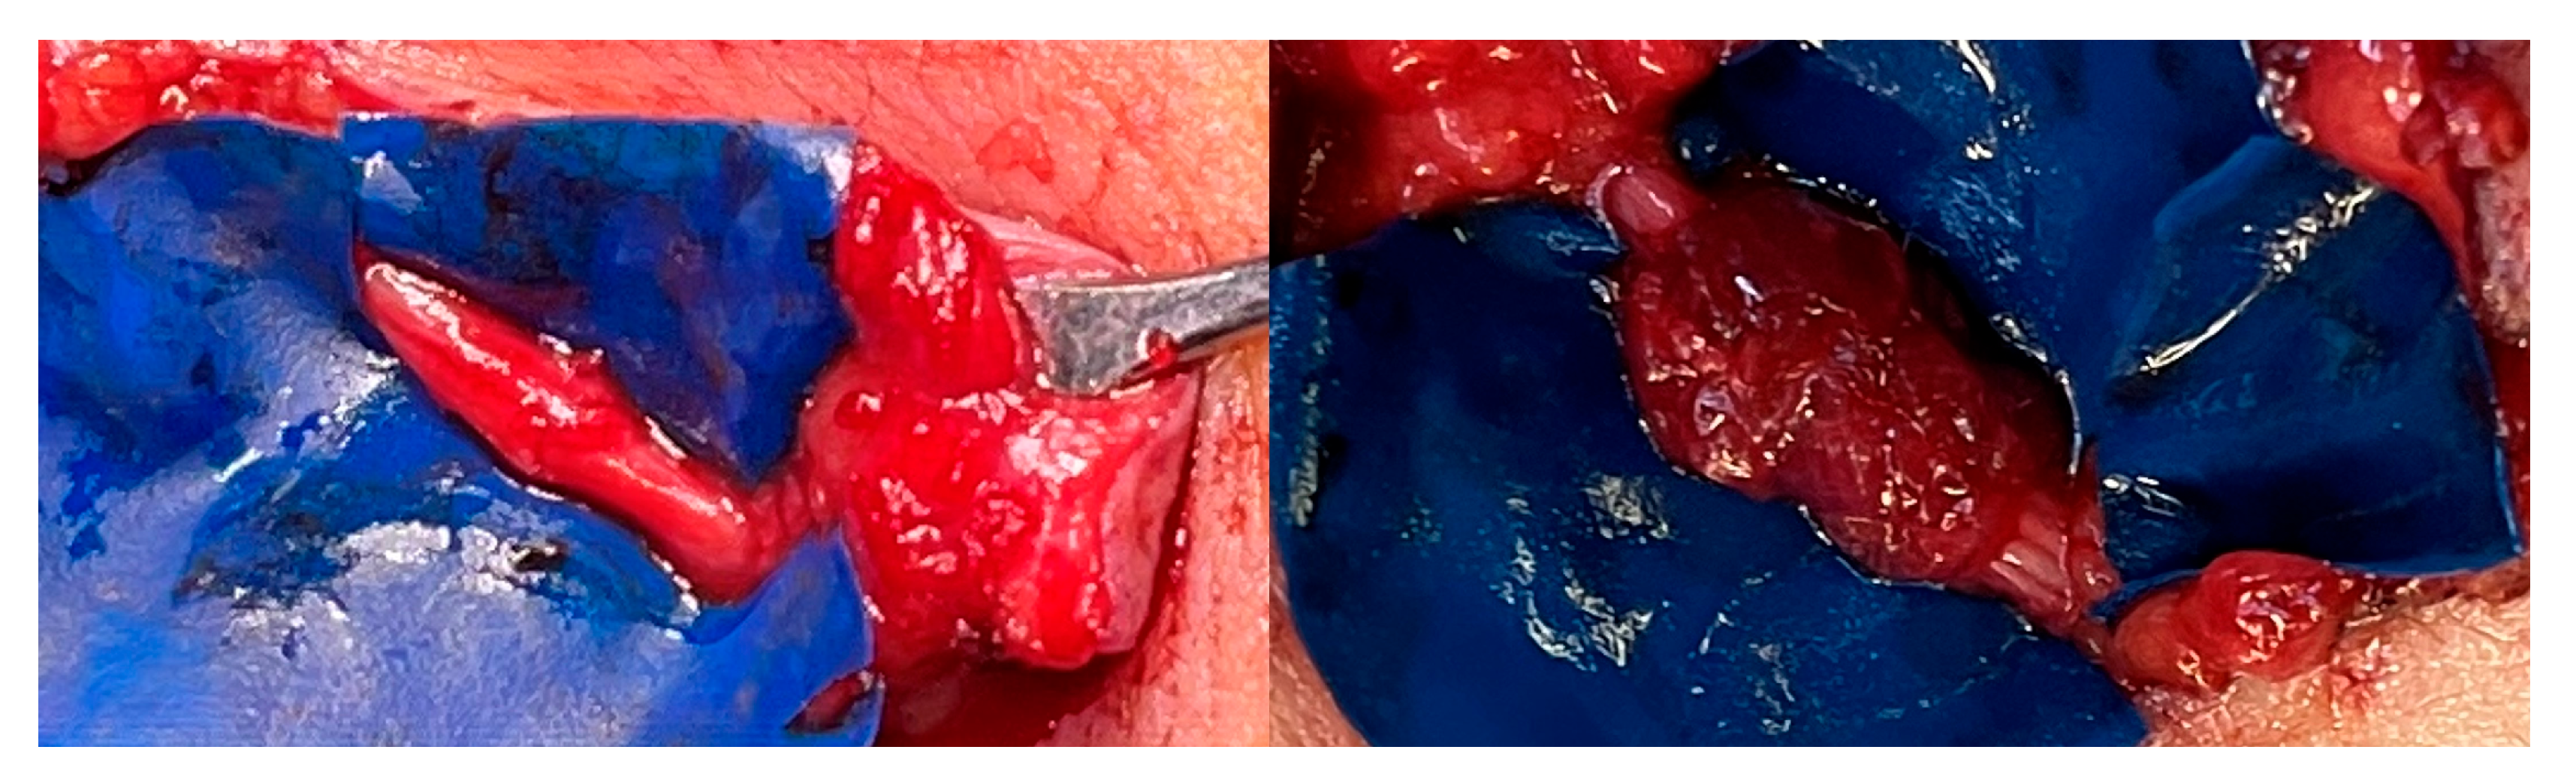

2.2. Surgical Technique